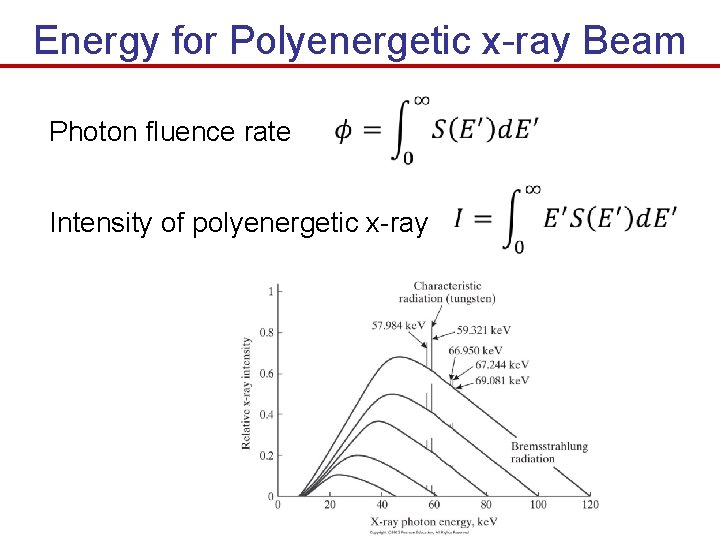

Energy for Polyenergetic x-ray Beam Photon fluence rate Intensity of polyenergetic x-ray